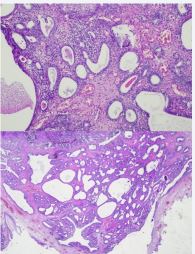

Cystoscopy revealed a papillary tumor lesion in the trigonal region. A monobloc resection with resection of the base of the tumor bed was performed and sent for anatomo-pathological study (Figure 1).

Histopathological examination found a benign tumor formation characterized by tubular proliferation of an adenomatous nature. Examination of the tumor bed reveals a urothelium with a small focus of squamous metaplasia resting on fibroblastic tissue.

Pathologically, tumor formation is characterized by an adenomatous tubular proliferation made up of elements of variable size and shape, sometimes distended or even cystic. Their epithelium does not show cytonuclear atypia and the interstitial tissue is inflammatory congestive. The base of the tumor bed has an epithelium with a focus of squamous metaplasia (Figures 2,3).